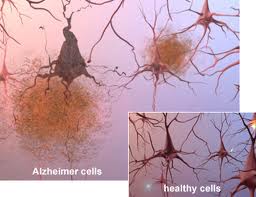

La enfermedad de Alzheimer es la forma más común de demencia. En el parénquima cerebral coexisten ovillos neurofibrilares intraneuronales, depósitos de amiloide extracelulares en forma de placas amiloides, angiopatía amiloide cerebral, y pérdida sináptica y neuronal, siendo las áreas límbicas las más severamente afectadas.

– Degeneración de las células ganglionares de la retina

lo que sugiere que ambas enfermedades pueden proceder de mecanismos de plegamiento similares. Una presentación de los caminos patogénicos comunes asociados con estos trastornos, incluyendo mecanismos de muerte celular, la producción de especies reactivas de oxígeno, la disfunción mitocondrial y anomalías vasculares, servirán como un punto de inicio para posteriores estudios.